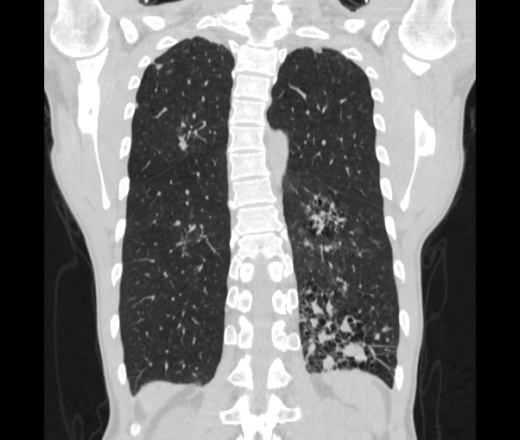

Мужчина пенсионного возраста. Цель назначения КТ ислючение зла в левом легком. Вижу тракционные бронхоэктазы с рубцовой эмфиземой по периферии, скорее всего БЭБ в стадии обострения. Дивертикулы трахеи. Выложил из за того что есть доля сомнения в отношении исключения зно3, немного смущают линии похожие на Керли.